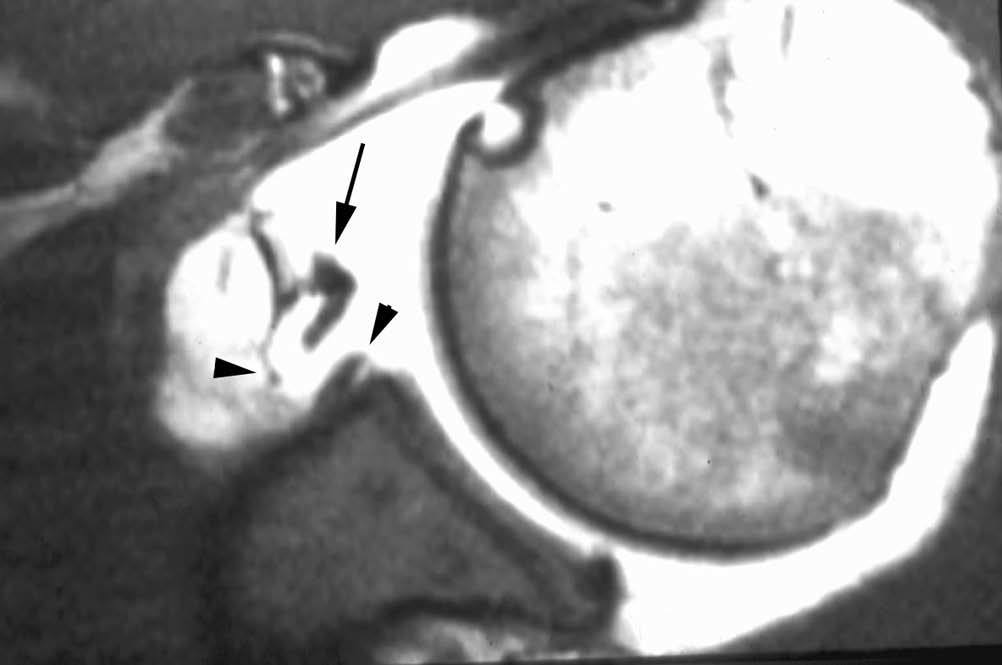

Esta lesión se produce a consecuencia de una tracción repetitiva de la unión cápsulo-perióstica posterior, produciéndose una osificación semejante a un espolón óseo (fig. 15).

Fig. 15.--Lesión de Bennett. Tomografía axial computarizada (TAC) axial (A) y resonancia magnética (RM) T1 axial (B) que revelan la presencia de un «espolón» óseo adyacente al borde glenoideo posterior (flechas en A y B). Nótese la ausencia de una lesión del labio glenoideo posterior en B.